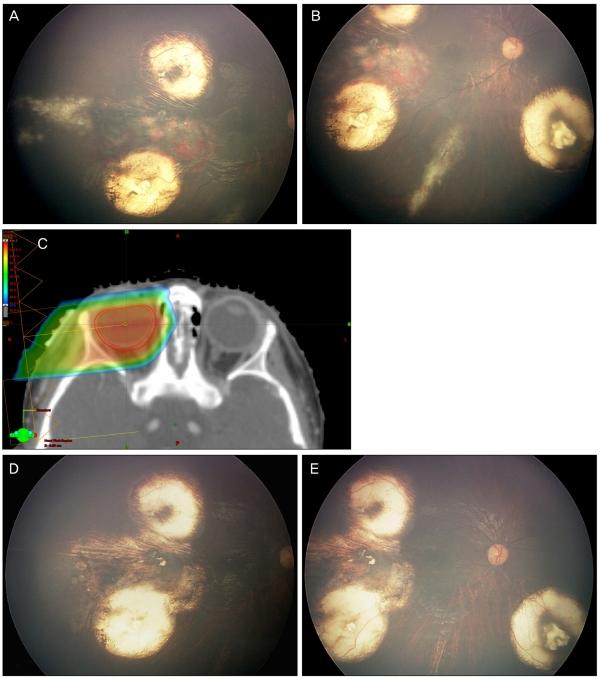

There were three patients who received PBRT. The first patient received PBRT because of an initial lack of tumor regression with chemotherapy and brachytherapy. This patient showed regression after PBRT. The second patient who developed recurrence of retinoblastoma as diffuse infiltrating subretinal seeding was taken PBRT. After complete regression, there was recurrence of tumor and the eye was enucleated. The third patient had unilateral extensively advanced retinoblastoma. Initial chemotherapy failed and tumor recurred. The tumor responded to PBRT and regressed significantly. However, the eye developed sudden multiple recurrences, so we had to perform enucleation.

有3例患者接受了PBRT。首例患者因化疗和近距离放疗后肿瘤最初未消退而接受PBRT。该患者在PBRT后肿瘤消退。第二例视网膜母细胞瘤复发为弥漫性浸润性视网膜下种植的患者接受了PBRT。完全消退后,肿瘤复发,该眼被摘除。第三例患者患有单侧广泛进展性视网膜母细胞瘤。初始化疗失败且肿瘤复发。肿瘤对PBRT有反应并显著消退。然而,该眼突然出现多处复发,因此我们不得不进行眼球摘除术。